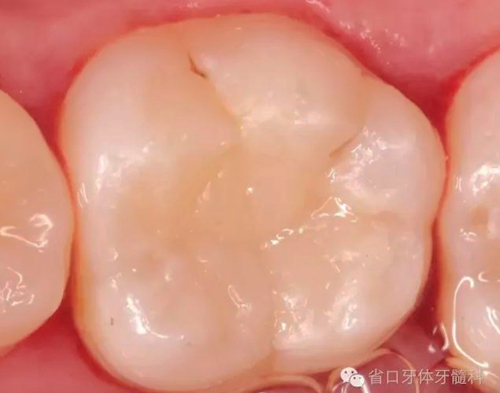

(圖16)取下“印章”,稍作修整

(圖17)光固化后

(圖18)拆除橡皮障,初步調(diào)整咬合

(圖19)進一步修整,拋光

“印章法”對于頜面窩溝點隙的隱匿性齲壞,頜面解剖形態(tài)完整的病例比較適用,不僅提高了窩溝塑性的效率和準(zhǔn)確性,能大大節(jié)約臨床操作時間,而且因為是直接原形態(tài)復(fù)制,所以完成后基本不需要太多調(diào)合,能節(jié)約不少椅旁時間,也在最大程度上保護了原有的咬合關(guān)系,在美觀上也能符合患者及醫(yī)生自己的要求。